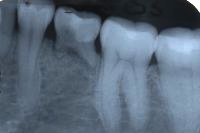

Eine 31 Jahre alte Patientin hatte akute Schmerzen am zweithintersten Backenzahn im Unterkiefer rechts und kam am 26. März 1980 zu uns in die Praxis.

Im Röntgenbild von Abb. 3 ist ein gut erbsengrosses Granulom (Pfeil) an der Wurzelspitze eines toten, devitalen Zahnes feststellbar. Die Patientin wünschte die Erhaltung des Zahnes, zumal auch der vordere Nachbarzahn marktot und beherdet war. Abb. 4 zeigt das Röntgenbild nach der Wurzelfüllung.

Ein halbes Jahr später hat die Patientin sich dazu entschlossen, den vorderen beherdeten Zahn auch endodontisch behandeln zu lassen. An Abb. 5 wird im Röntgenbild die Wurzellänge mit Instrumenten bestimmt. Man gewinnt auch den Eindruck, dass der bereits vor einem halben Jahr wurzelbehandelte Zahn in Abheilung sei.

Wieder ein Jahr später machen wir ein Routineröntgenbild der beiden wurzelbehandelten Zähne und stelle beim hinteren Zahn einen beinahe haselnussgrossen Herd fest (Abb. 6). Der Zahn ist zwar schmerzfrei, aber sicher nicht entzündungs- und keimfrei; möglicherweise ist es sogar eine Zyste?